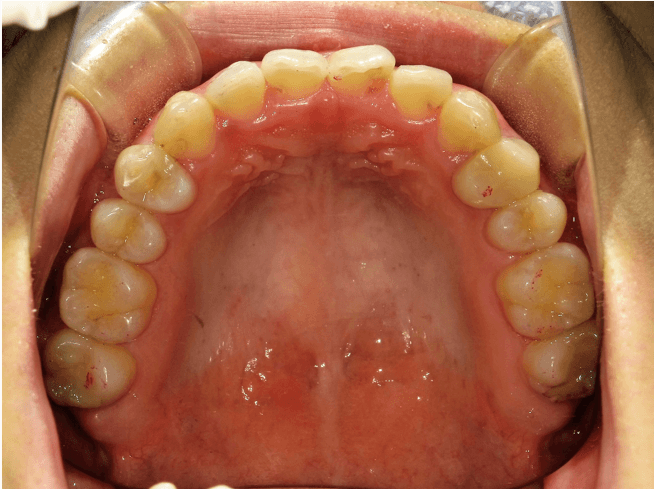

叢生(軽度)

BEFORE

AFTER

担当医コメント

上下に軽度の叢生がある。IPRと歯列の拡大で改善可能と考えインビザラインで治療を行うことにしました。

IPRは被せ物や銀歯の部位に集中させて、歯にかかる負担をなるべく少なくなるように計画した

治療の概要

年齢/性別

26歳 女性

主訴

上下の歯並びが気になる

リスク

歯肉退縮が起こる可能性がある。

費用

82万円(矯正費用)

期間

1 5 ヶ月